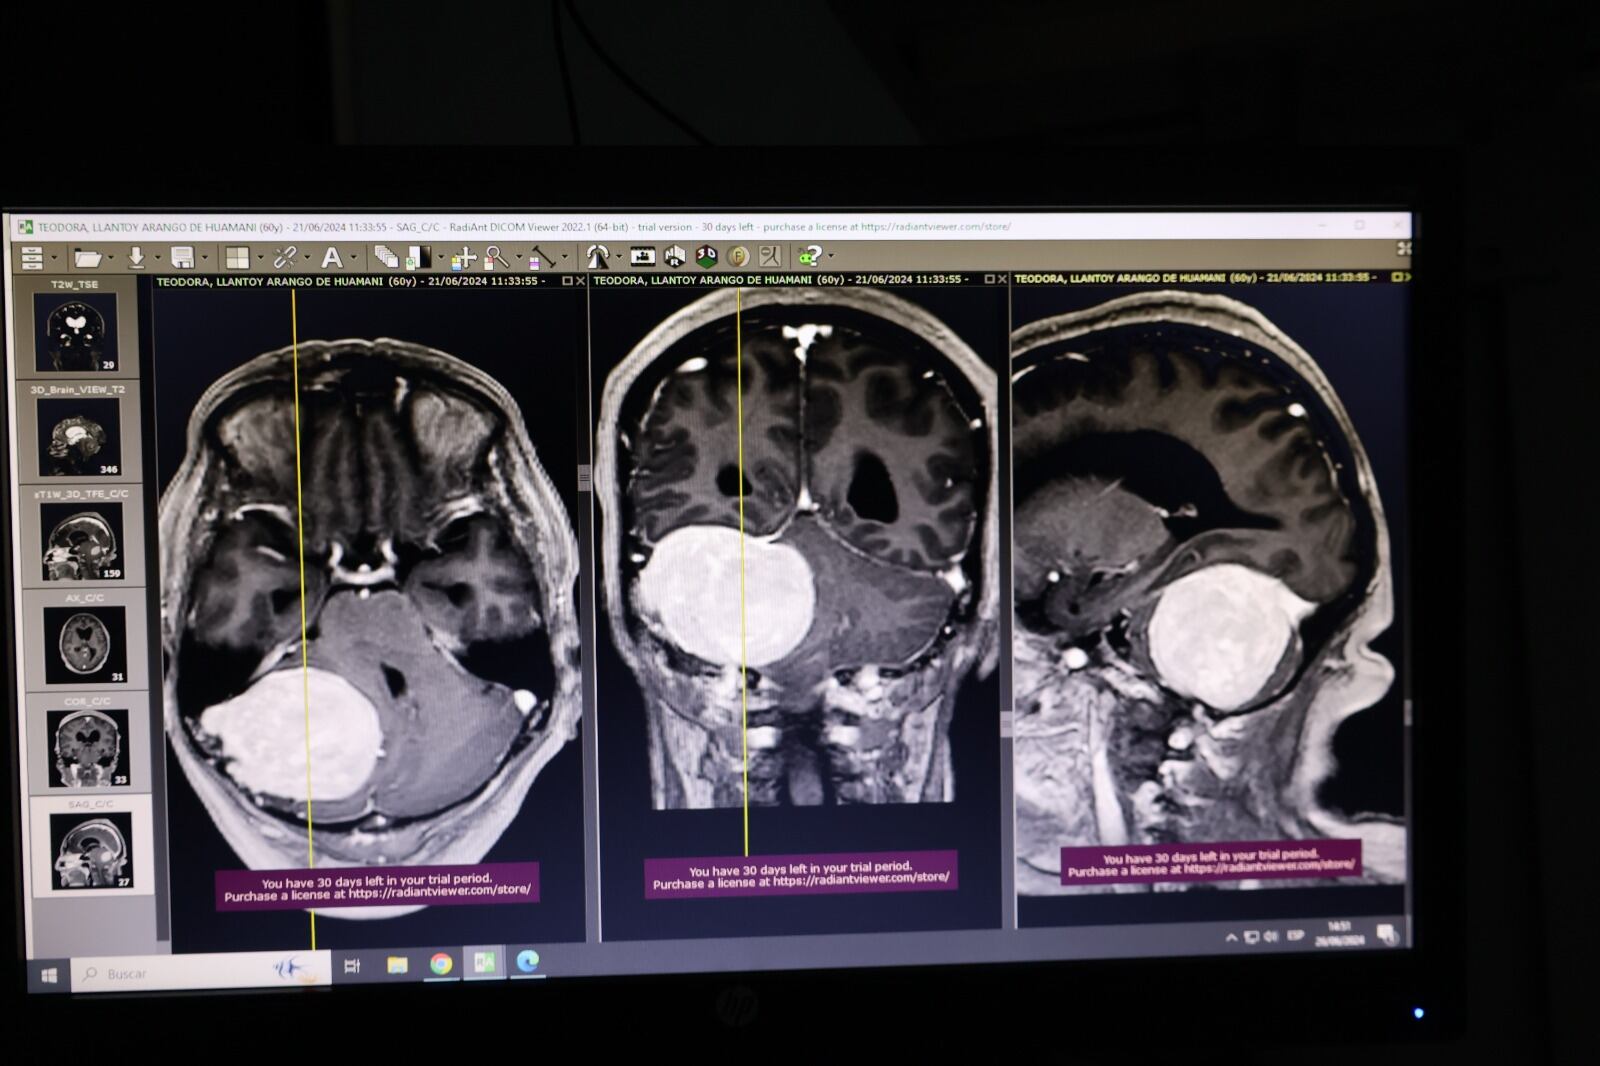

El paciente sexagenario, natural de Tayacaja – Huancavelica, ingresó de emergencia al hospital, con un tumor ubicado en el cerebelo, una región crítica del cerebro que controla la coordinación motora y el equilibrio. El tumor, de 8 cm x 7 cm x 6 cm, no solo había limitado neurológicamente a la paciente, sino que también la ponía en riesgo de morir en cualquier momento debido a la gran presión que ejercía sobre su cerebro.

La intervención, liderada por el médico neurocirujano Iván Paucar Calderón, con un equipo multidisciplinario, que incluyó a especialistas en neurocirugía, enfermeras, técnicos y otros profesionales de la salud. “Estamos procediendo a la resección, es decir, al retiro total del tumor de esta región para que nuestra paciente pueda recobrar la salud que había sido dañada por esta enfermedad”, detalló el neurocirujano.